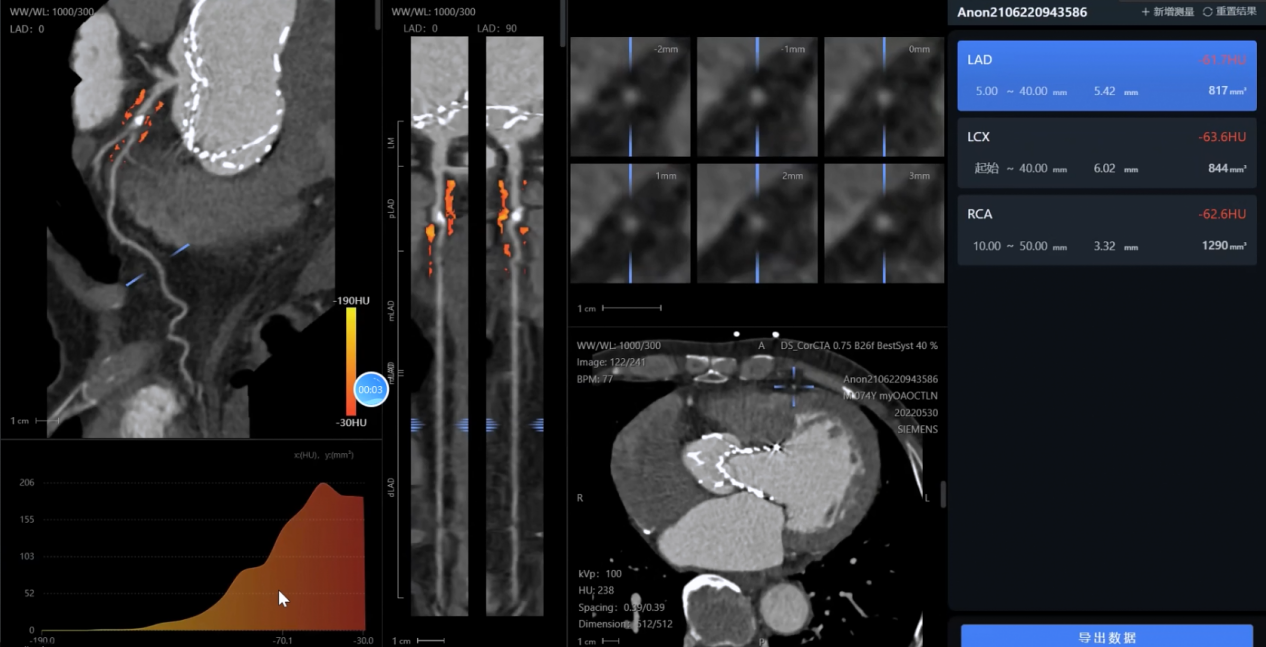

影像智能分析:對(duì)CTA、MRA等多模態(tài)影像進(jìn)行自動(dòng)處理和病變識(shí)別

影像分析方面:系統(tǒng)能夠自動(dòng)處理心血管CTA、腦血管MRA、外周血管超聲等多模態(tài)影像數(shù)據(jù),精準(zhǔn)識(shí)別斑塊性質(zhì)、狹窄程度和病變范圍,生成結(jié)構(gòu)化報(bào)告。

綜合評(píng)估方面:啄醫(yī)生大模型整合患者臨床資料、實(shí)驗(yàn)室檢查和影像學(xué)結(jié)果,構(gòu)建個(gè)體化的泛血管健康指數(shù),全面評(píng)估全身血管健康狀況。